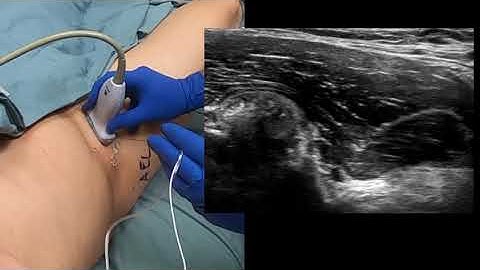

Download lagu PENG Block (Pericapsular Nerve Group Block) secara gratis hanya untuk keperluan promosi.